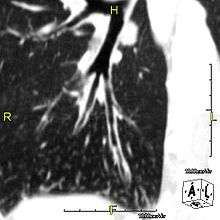

When accompanied by the combination of situs inversus (reversal of the internal organs), chronic sinusitis, and bronchiectasis, it is known as Kartagener syndrome (only 50% of primary ciliary dyskinesia cases include situs inversus).

The main consequence of impaired ciliary function is reduced or absent mucus clearance from the lungs, and susceptibility to chronic recurrent respiratory infections, including sinusitis, bronchitis, pneumonia, and otitis media. Progressive damage to the respiratory system is common, including progressive bronchiectasis beginning in early childhood, and sinus disease (sometimes becoming severe in adults). However, diagnosis is often missed early in life despite the characteristic signs and symptoms.[1] In males, immotility of sperm can lead to infertility, although conception remains possible through the use of in vitro fertilization and, as well as this, there have been reported cases where sperm were able to move.[2] Trials have also shown that there is a marked reduction in fertility in female sufferers of Kartagener's Syndrome due to dysfunction of the oviductal cilia.[3]

Many affected individuals experience hearing loss and show symptoms of glue ear which demonstrate variable responsiveness to the insertion of myringotomy tubes or grommets. Some patients have a poor sense of smell, which is believed to accompany high mucus production in the sinuses (although others report normal - or even acute - sensitivity to smell and taste). Clinical progression of the disease is variable with lung transplantation required in severe cases. Susceptibility to infections can be drastically reduced by an early diagnosis. Treatment with various chest physiotherapy techniques has been observed to reduce the incidence of lung infection and to slow the progression of bronchiectasis dramatically. Aggressive treatment of sinus disease beginning at an early age is believed to slow long-term sinus damage (although this has not yet been adequately documented). Aggressive measures to enhance clearance of mucus, prevent respiratory infections, and treat bacterial superinfections have been observed to slow lung-disease progression. Although the true incidence of the disease is unknown, it is estimated to be 1 in 32,000,[4] although the actual incidence may be as high as 1 in 15,000.